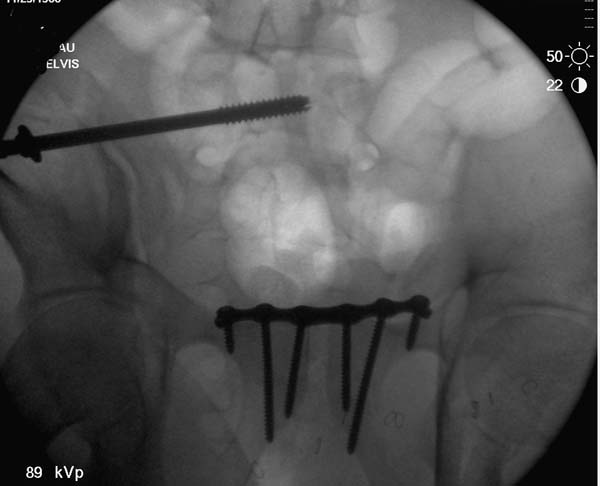

Но вам повезло, двумя винтами смогли зацепить и репонировать

переломо-вывих. Обычно такие переломы надо фиксировать спереди или сзади

пластиной или шурупом, т.е. создать дополнительную стабильность крыла,

кроме  перкутанной фиксации.

Техника репозиции вытяжением работает намного лучше, когда конечность в

согнутом положении, потому что нейтрализируются абдоминальные мышцы.

Вместо больших грузов, сгибание лучший прием для репозиции. А все

Здесь примеры фиксации с различными вариантами.... .